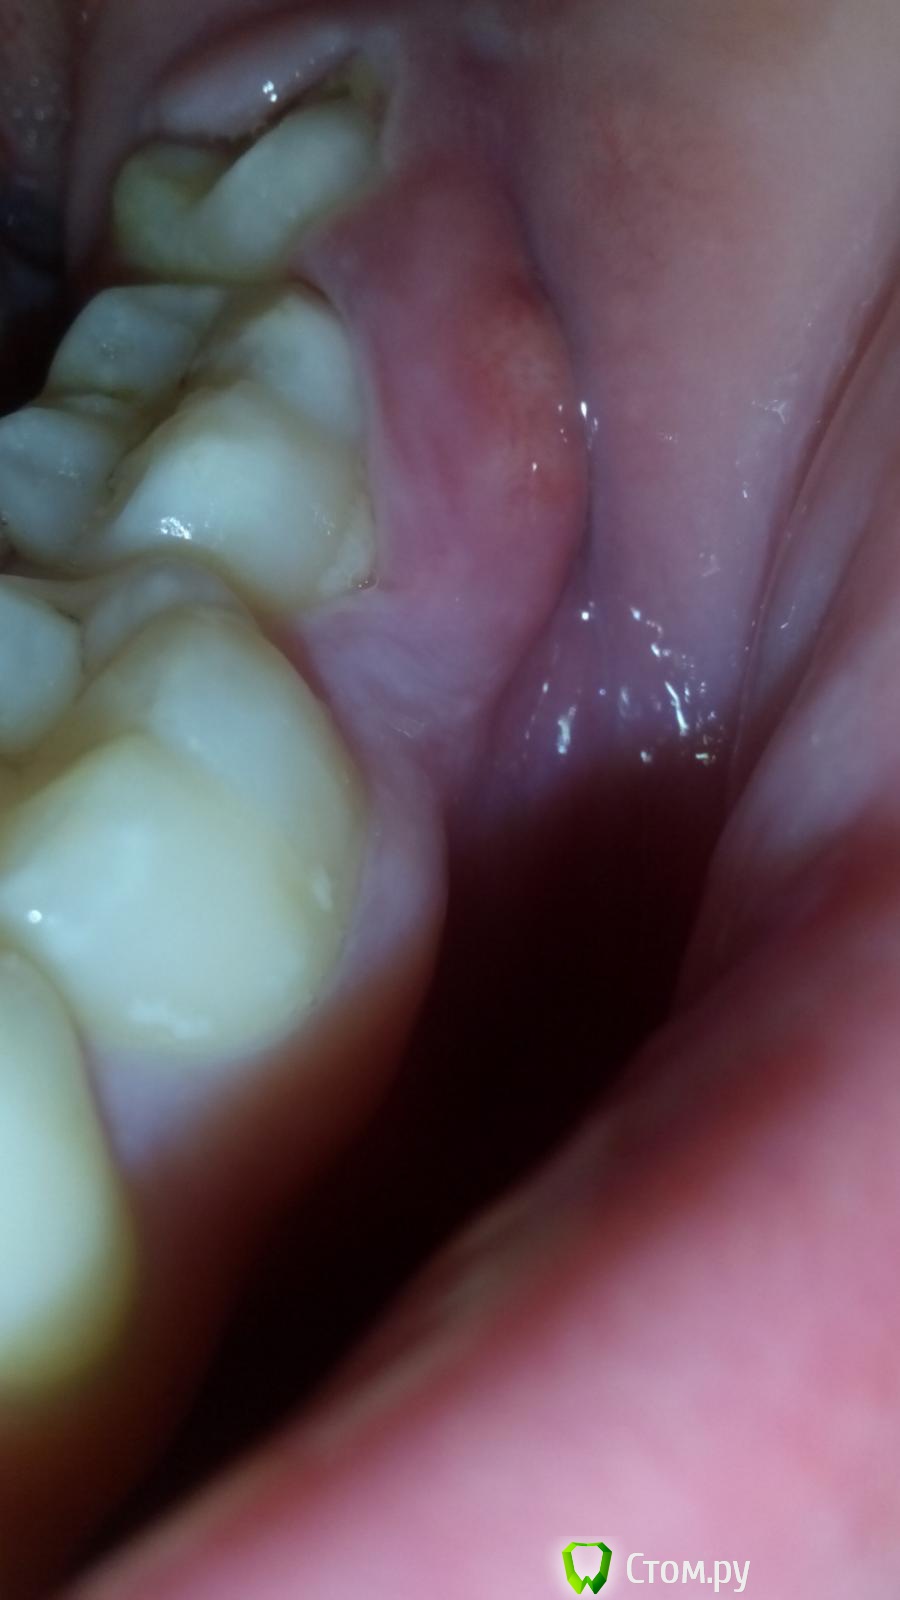

saadun Опубликовано 27 июня, 2014 Поделиться Опубликовано 27 июня, 2014 2-3 дня уже с воспалением хожу ночью болело, днём как будто и нет, надеялся, что поможет полоскание. Знаю что надо было сразу, завтра пойду к врачу, но хочется узнать что это ? Нервничаю, ещё пару часов назад начало болеть место воспаления. Ссылка на комментарий

Korel Опубликовано 28 июня, 2014 Поделиться Опубликовано 28 июня, 2014 но хочется узнать что это ? Перикоронарит Нервничаю Знаю что надо было сразу, завтра пойду к врач Раз знаете - делайте. Ссылка на комментарий